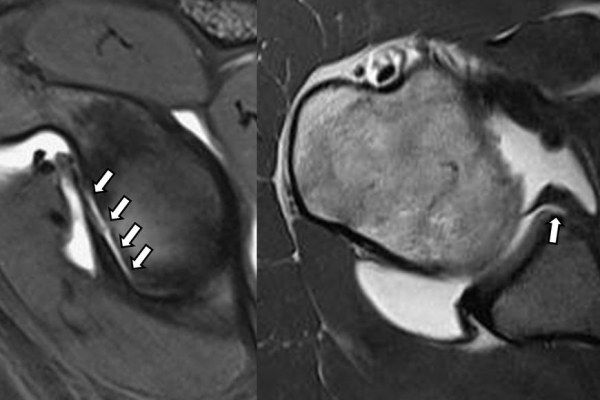

Είναι μια ελάχιστα επεμβατική απεικονιστική μέθοδος που επιτρέπει τη λεπτομερέστερη διερεύνηση του εσωτερικού των αρθρώσεων. Η ασφαλής έγχυση σκιαγραφικού εντός της άρθρωσης υπό ακτινολογική καθοδήγηση και η ακόλουθη απεικόνιση της άρθρωσης με αξονική ή μαγνητική τομογραφία (ή και με συνδυασμό των μεθόδων) αποσαφηνίζει βλάβες του χόνδρου και κακώσεις-ρήξεις συνδέσμων και τενόντων με υψηλή ακρίβεια, συμβάλλοντας σημαντικά στο λεπτομερή χειρουργικό σχεδιασμό.